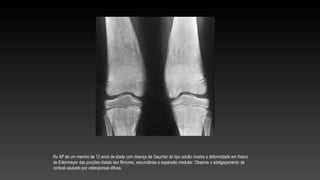

Rx AP de um menino de 12 anos de idade com doença de Gaucher do tipo adulto mostra a deformidade em frasco

de Erlenmeyer das porções distais dos fêmures, secundárias a expansão medular. Observe o adelgaçamento da

cortical causado por osteoporose difusa.